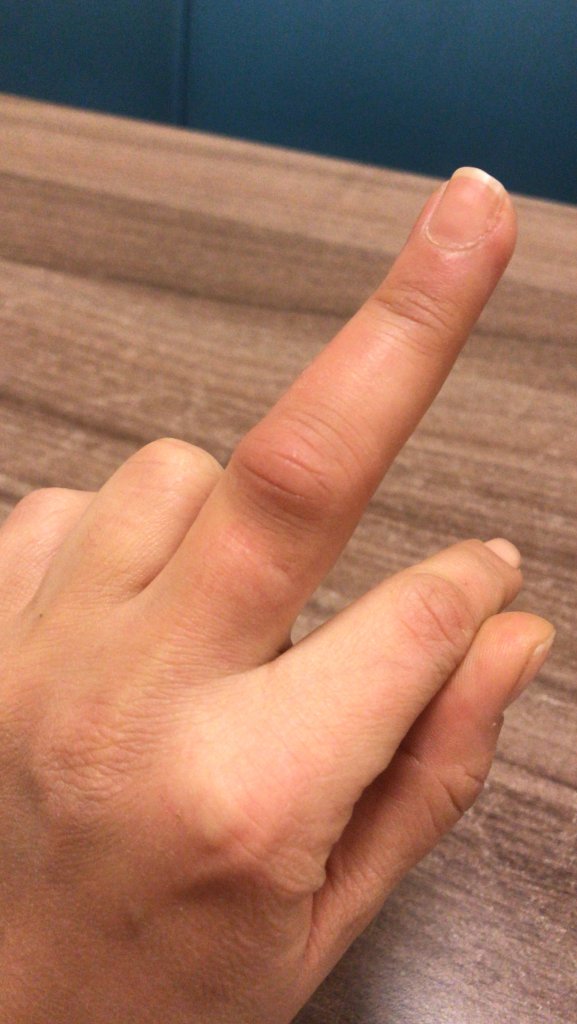

Eşim le voleybol oynarken topa nasıl vurdum bilmiyorum parmağım burkuldu mu çarptı mı döndü mü anlamadım ağrımaya başladı daha sonra kızarıklık şişme oluştu sabah acil servise gittim röntgen çekti acil Dr kırık çatlak yok dedi atel taktı ağrı kesici buz komplesi krem yazdı işe geldim ancak parmak git gide şişiyor ve hareket muhtemelen şişlikten dolayı sınırlanıyor anlamamış olabilir mi Dr sanmıyorum ama tendon diye bişey duydum ilk defa ne olduğunu da anlamadım röntgen de anlaşılmaz mıydı doku zedelenmesi daha önce yaşadım elim de çatladı ayağımda kırıldı  herşey başıma gelmiş şaka gibi böyle şişmedi hiç bu durumu yaşayan var mı aramızda yada benzer bişey aşma aşama resim ekledim ultrason anlayan vardır diye onu da koydum

herşey başıma gelmiş şaka gibi böyle şişmedi hiç bu durumu yaşayan var mı aramızda yada benzer bişey aşma aşama resim ekledim ultrason anlayan vardır diye onu da koydum